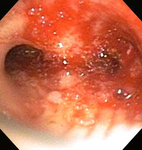

Стеноз дыхательных путей на фоне гранулематоза с полиангиитом (ранее именуемого гранулематозом Вегенера)

Из коллекций Хосе Фернандо Сантакруза, дипломированного врача, члена Американской коллегии специалистов в области торакальной медицины, DAABIP, и Эрика Фолка, дипломированного врача, магистра наук; используется с разрешения